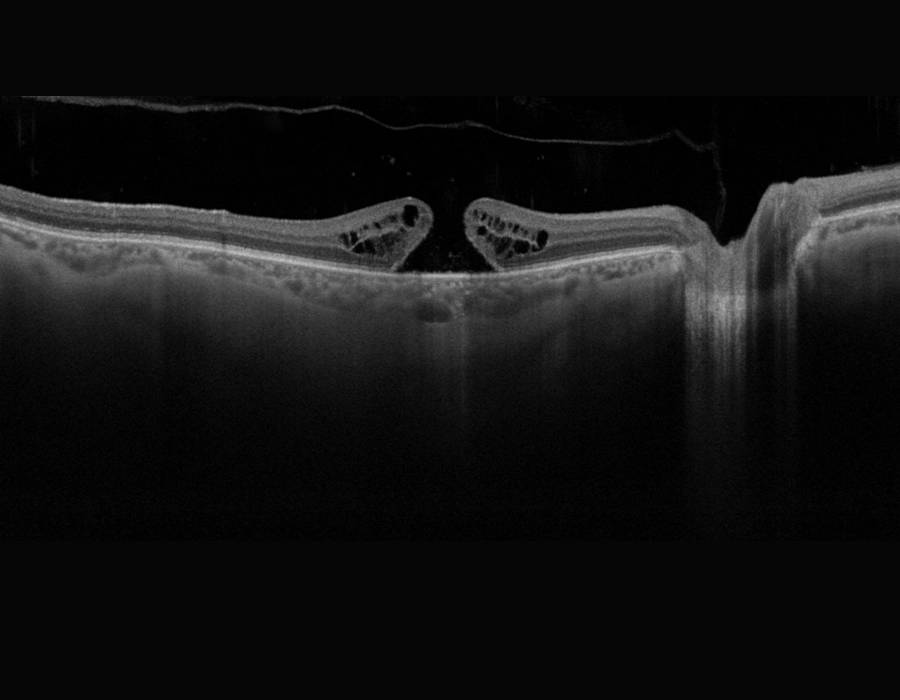

- OCT (optical coherence tomography) is a non-invasive scan of the retina which confirms the diagnosis. OCT takes cross-sectional images of the retinal layers and helps in ruling out other similar-looking diseases of the eye. It also helps to pick up any early changes in the fellow eye.

In 2013, the International Vitreomacular Traction Study Group also formed a classification scheme of vitreomacular traction and macular holes based on OCT findings (1,3)

- Vitreomacular adhesion: No distortion of the foveal contour; size of attachment area between hyaloid and retina defined as focal if ≤1500 microns and broad if >1500 microns

- Vitreomacular traction (VMT): Distortion of foveal contour present or there are intraretinal structural changes in the absence of a full-thickness MH; size of attachment area between hyaloid and retina defined as focal if ≤1500 microns and broad if >1500 microns

- Full-thickness macular hole (FTMH): Full-thickness defect from the internal limiting membrane (ILM) to the retinal pigment epithelium. Size is based on the horizontal diameter at the narrowest point: small (≤250 μm); medium (250–400 μm); or large (>400 μm). The cause may be primary or secondary, and VMT may be present or absent